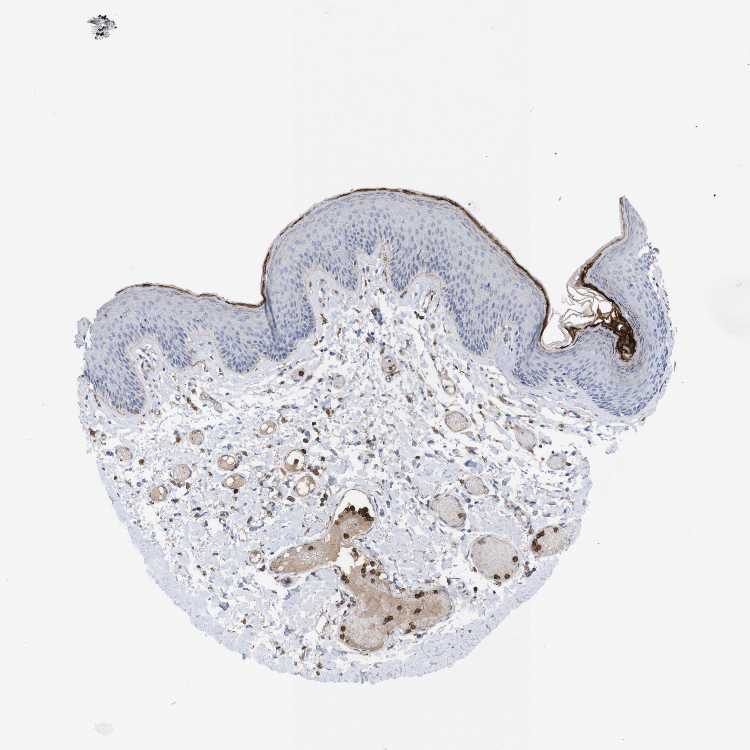

SKIN 2 - Antibody stainingi

Antibody staining in the annotated cell types in the current human tissue is reported as not detected, low, medium, or high, based on conventional immunohistochemistry profiling in selected tissues. This score is based on the combination of the staining intensity and fraction of stained cells.

Each image is clickable and will lead to virtual microscopy that enables deeper exploration of all samples and also displays staining intensity scores, fraction scores and subcellular localization as well as patient and tissue information for each sample.

Antibody HPA014520Antibody CAB002720

Epidermal cells Not detectedMedium